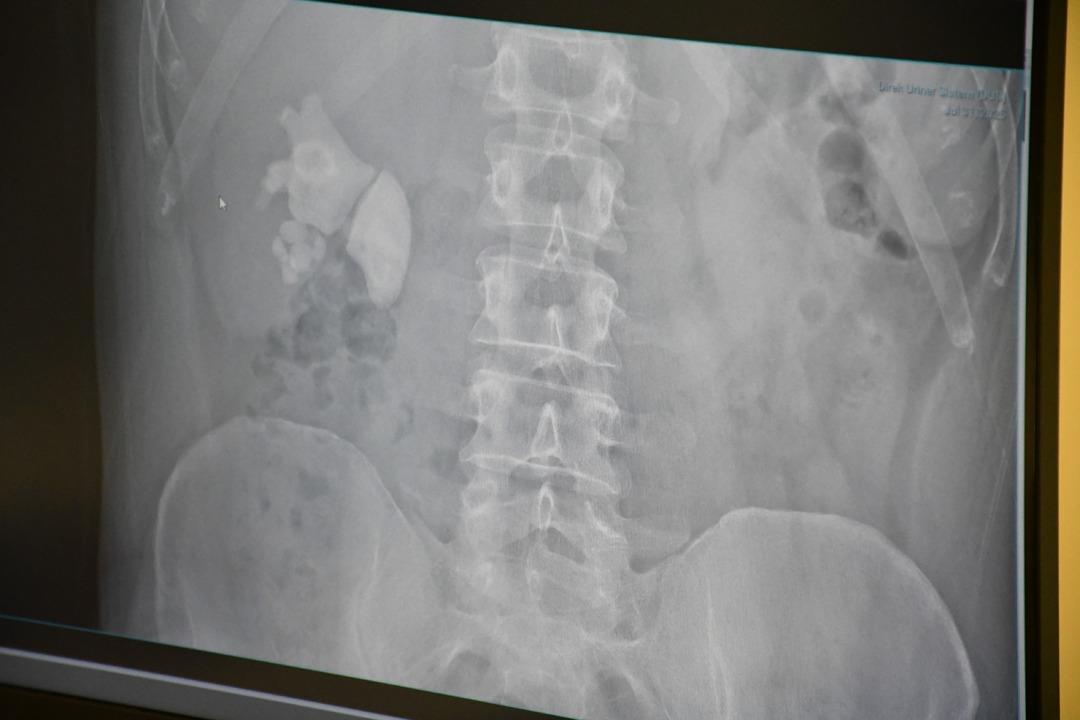

Doktorları şaşkına çeviren vaka: Adamın böbreğinden 100’e yakın taş çıktı: “Sağ böbreğin tamamı taşla doluydu”

Kendilerini şiddetli böbrek ağrısı ile Yozgat şehrinin hastanesine uygulayan Evran'ın ayrıntılı sınavlarının ardından böbrekte yaklaşık 100 taş tespit edildi.

“Tamam böbrek taş doluydu”

Kamocanoglu, “Sağ böbrek muayenemiz taşlarla doluydu. Hasta hastayla tanıştı ve bu kadar büyük taşlarda büyük bir ameliyat olabilir ve hasta bazı deliklere girdi, ameliyatın sırtını gerçekleştirerek yapılması gerektiğini söyledi. Hasta kabul etti. Hasta ameliyatını Çarşamba günü yaptık.”